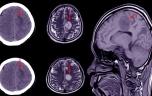

Une ecchymose ou un hématome correspondent à une collection de sang sous la peau, dans un muscle ou dans un organe. La quantité de sang est plus importante au cours d’un hématome. Selon sa cause, son importance ou sa localisation un hématome peut poser problème.

Une ecchymose ou un hématome correspondent à une poche de sang sous la peau, dans un muscle ou dans un organe.